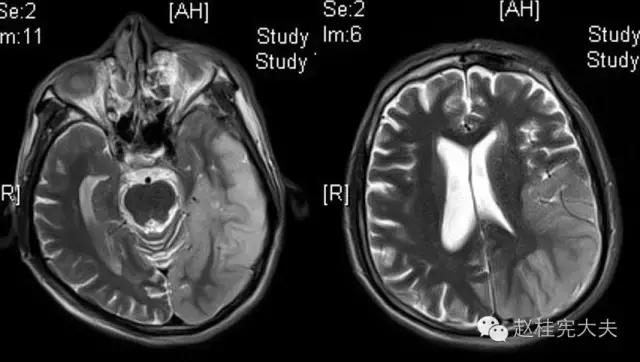

完善检查,头颅MRI回报:左侧颞顶枕叶急性梗死灶。

当看到磁共振片子的时候,我知道,我们忽略了一些东西......

患者的磁共振影像不符合脑血管病的血供分布,跨了大脑中动脉和大脑后动脉范围,且病灶偏皮层分布。大脑前、中、后动脉血供分布(横断面)见下图

这不是一个真的“脑卒中”,而是一个“卒中样发作”。